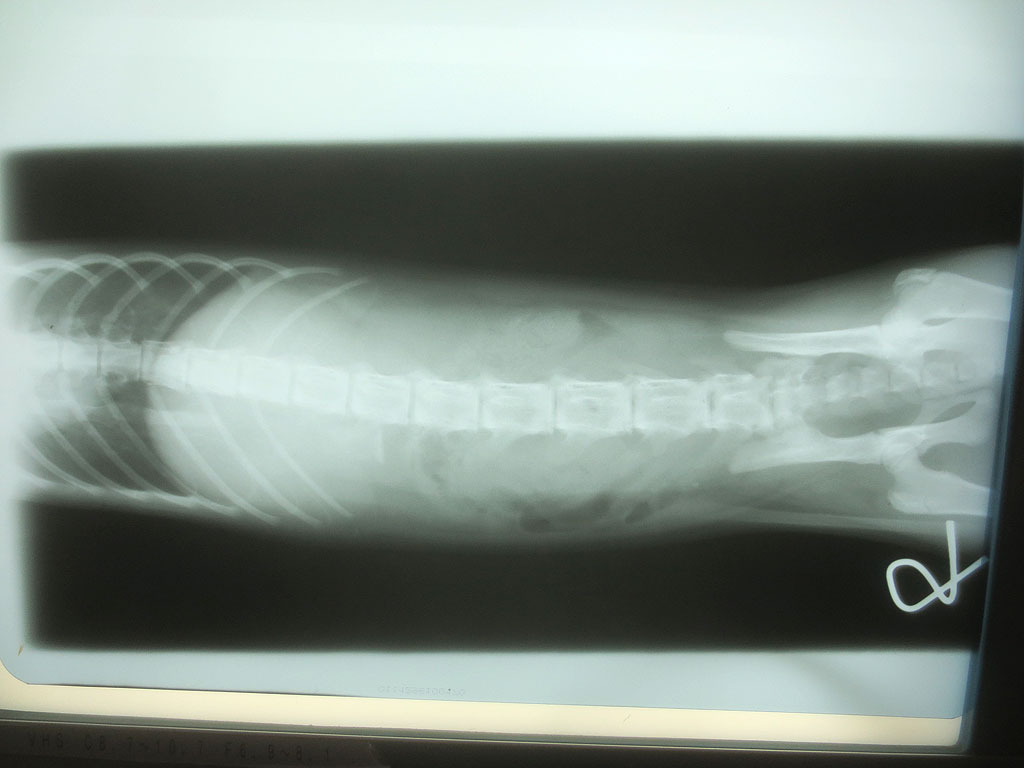

そして、レントゲンの現像も終わって、また診察室に呼ばれ、早速、レントゲンの写真を見せて頂いたのですが、いきなりですが、アビのすけの胃の中に異物が…。

紐とかだったらレントゲンに写らないそうなのですが、かなりはっきりと写っていて、何か、金属的なものを飲み込んでいるとの事…。

食パンの袋の口を結ぶ、芯に針金が入ったくるくるってひねって巻くやつの様だと先生はおっしゃったのですが、そんなものは部屋の中にはない筈なのですが、私が落としてしまったのかも知れず…。

全部で6枚、撮って頂いたのですが、後の5枚は、特に何も写っていなかったので、連続でアップさせて頂きます。